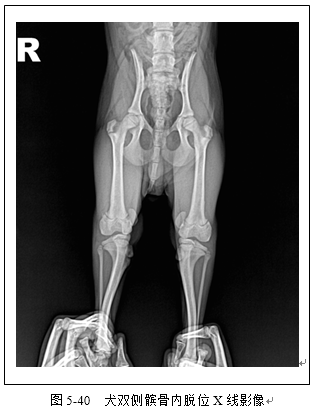

四肢骨骼X线评估常用于骨折检查(图5-36、5-37、5-38、5-39)以及关节脱位(5-40)检查。